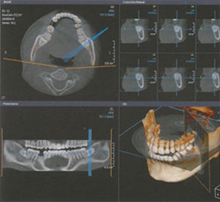

これは主に、インプラントや親知らずの抜歯などの治療に用いられます。 三次元の高画質画像を用いることで、断層方式パノラマX線写真や口内法X線撮影法(いわゆるレントゲンですね)では判別しにくい痛みや症状の原因の究明に役立ちます。

歯科用CTは、コーンビーム式のスキャンを行う事で、短時間のX線照射による、歪みの少ないな画像を断面でとても詳しく観察することができます。

歯科用CTと医科用CTとの大きな違いは、撮影方法が医科用は被写体(患者様)が横たわるのに対し、歯科用CTではどこのメーカーの装置でも座ったままでの撮影となることです。 また、撮影時間がかなり短く約10秒ほどで済みますので被爆線量が医科用の約10分の1と非常に少ないところも大きな違いとなります。 それでいて超高解像度画像から広範囲撮影まで選択可能で医科用CTの約5倍の情報量を得ることが可能です。

インプラント治療におけるCT検査のメリットはとても大きく、通常のレントゲンでは正確に確認できない神経管の位置やインプラント埋入部位の骨の状態が正確に解ります。そのため、骨造成が必要と思われた症例でも十分な骨量が確認でき、約6ヵ月間の治療期間短縮と手術の負担を軽減できることもあります。